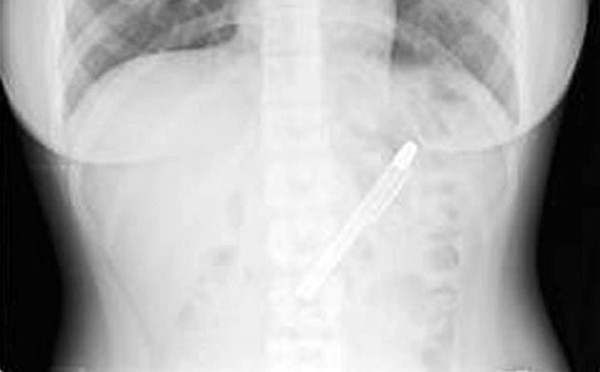

La radiografía que le hicieron no dejaba lugar a dudas del tipo de objeto que había permanecido en el estómago de la joven durante nada menos que seis meses.

Tenía un horroroso dolor de estómago que le impedía comer y finalmente decidió acudir al hospital de Taipei. Tras realizarle las pruebas pertinentes, el asombroso resultado dejó impresionado tanto a la paciente como al personal sanitario: había una pluma estilográfica alojada en el aparato digestivo de Shing Fang, una estudiante de 20 años residente en Taiwán.